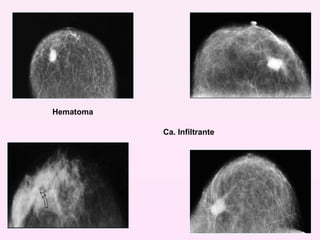

Hematoma Ca. Infiltrante